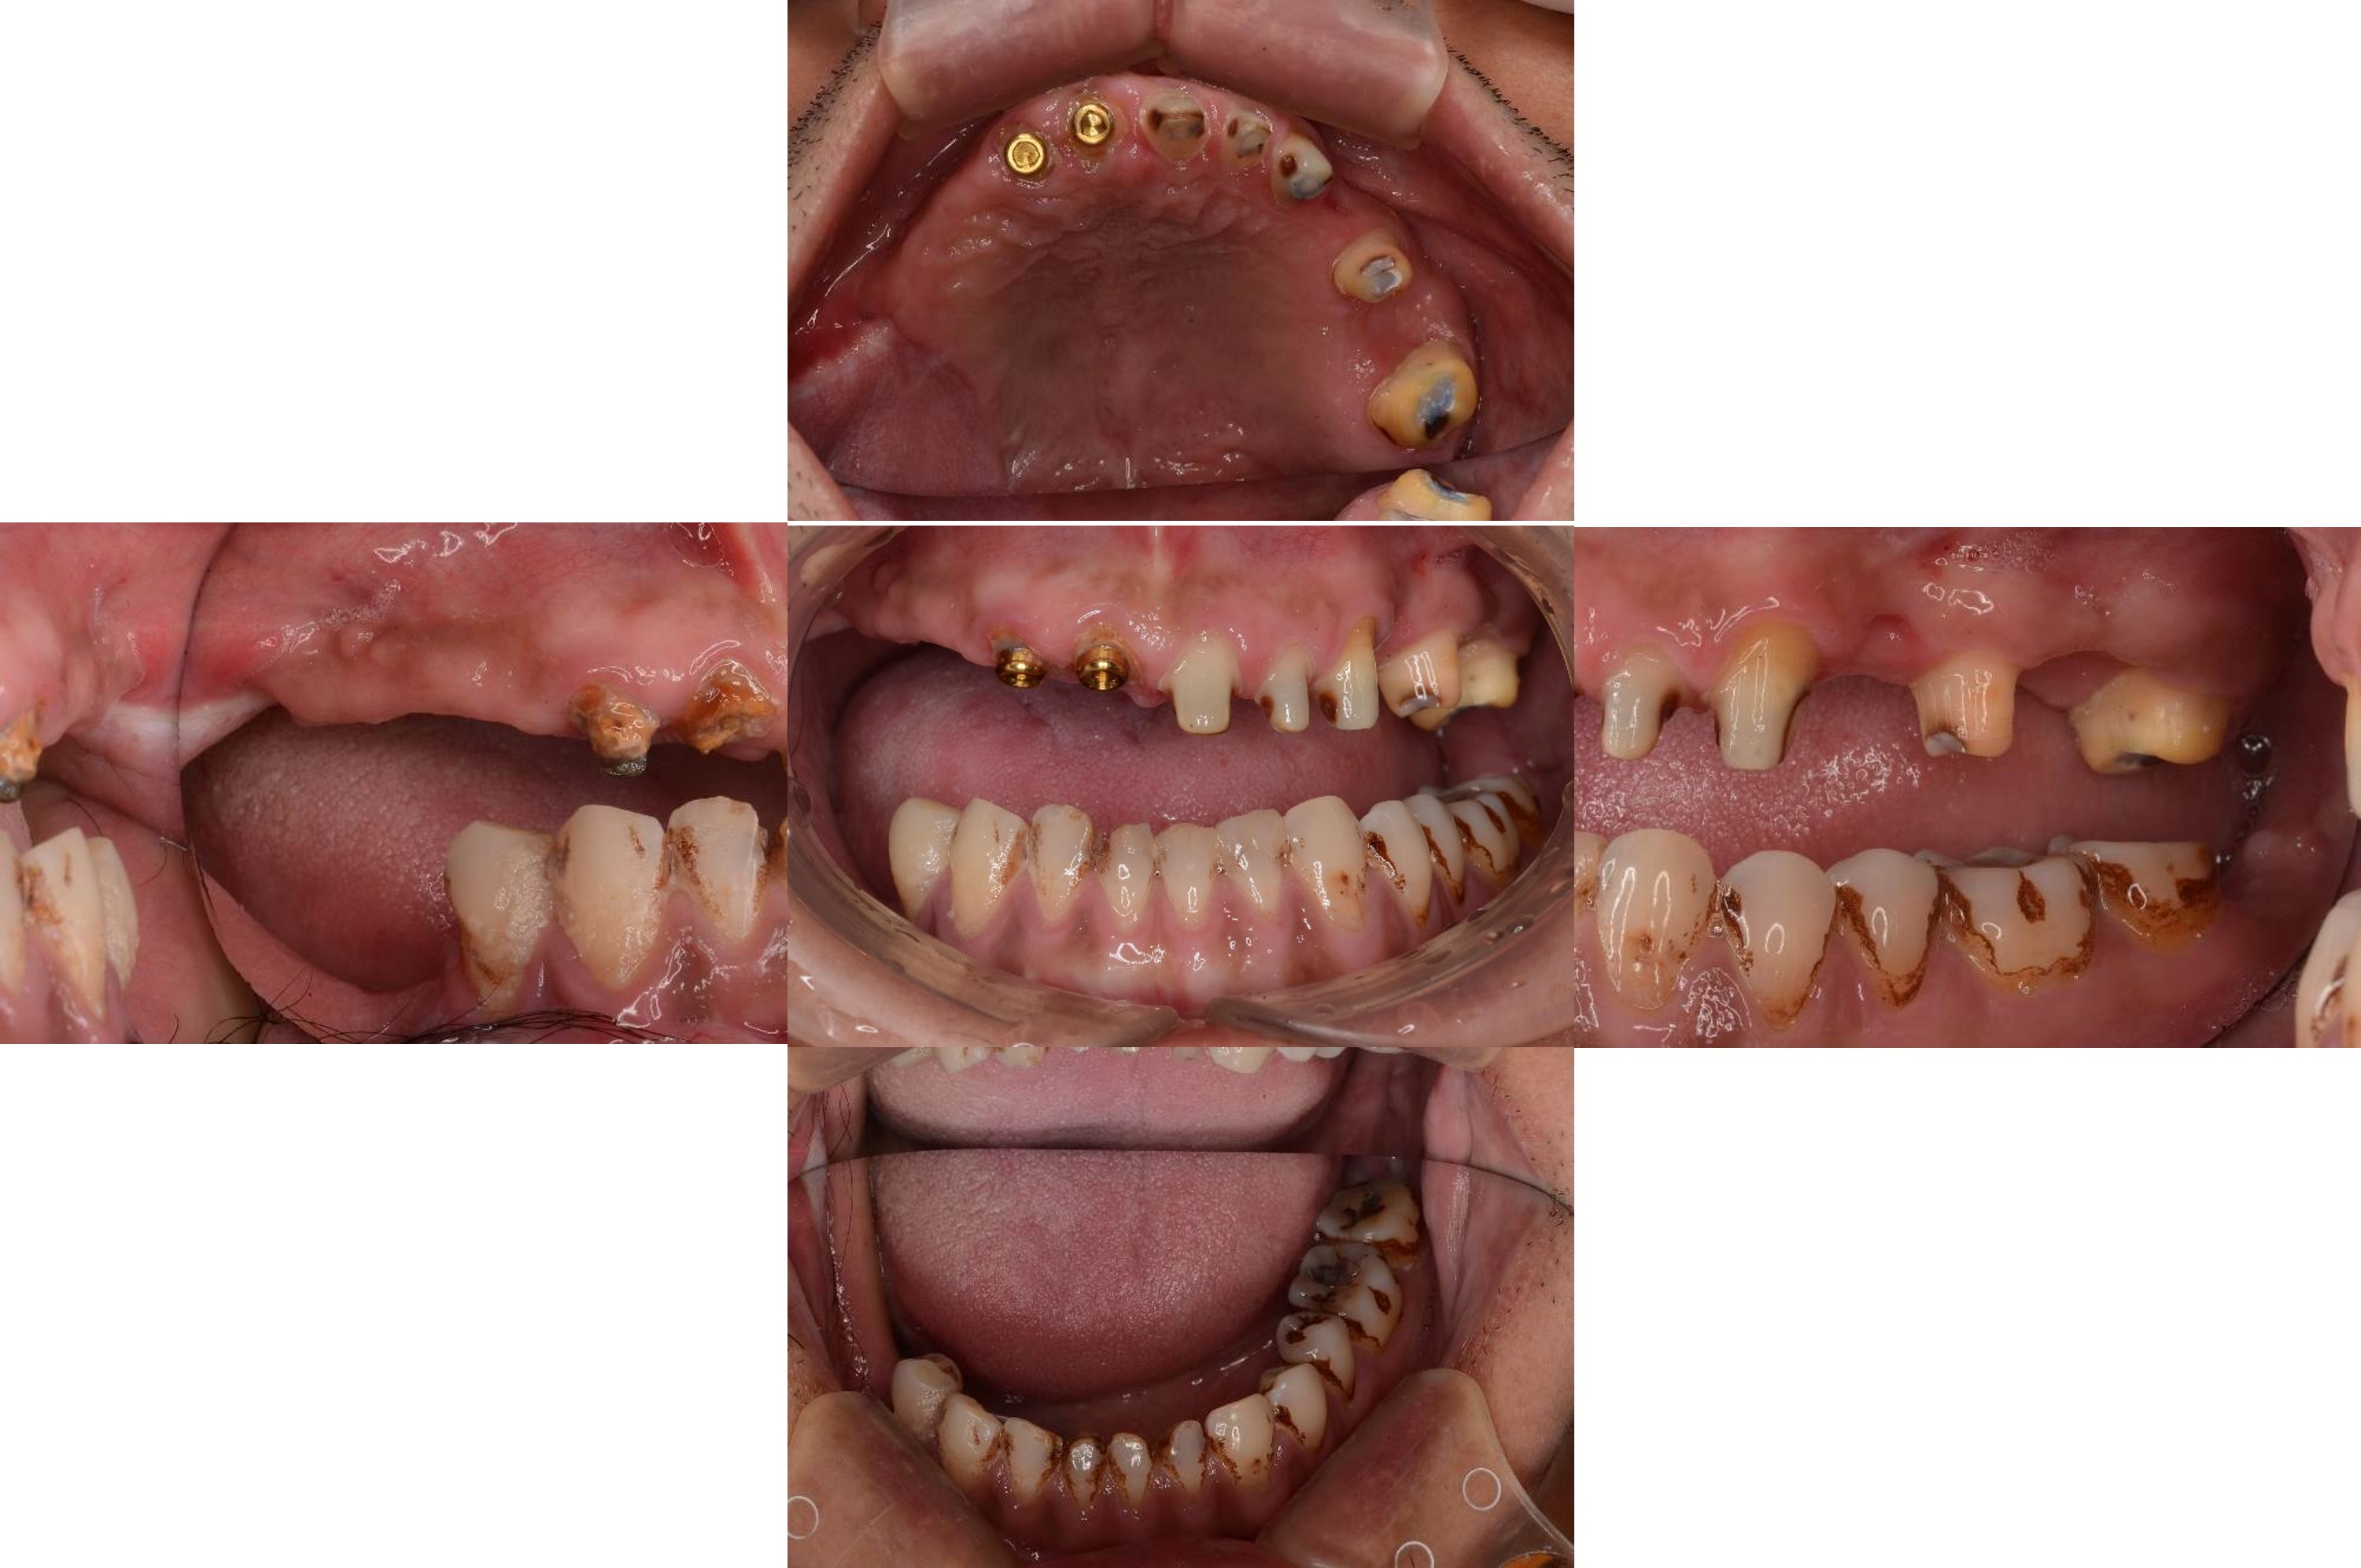

治療前,咬合喪失,磨耗

治療前,殘根與牙周支撐不良

膺復前評估